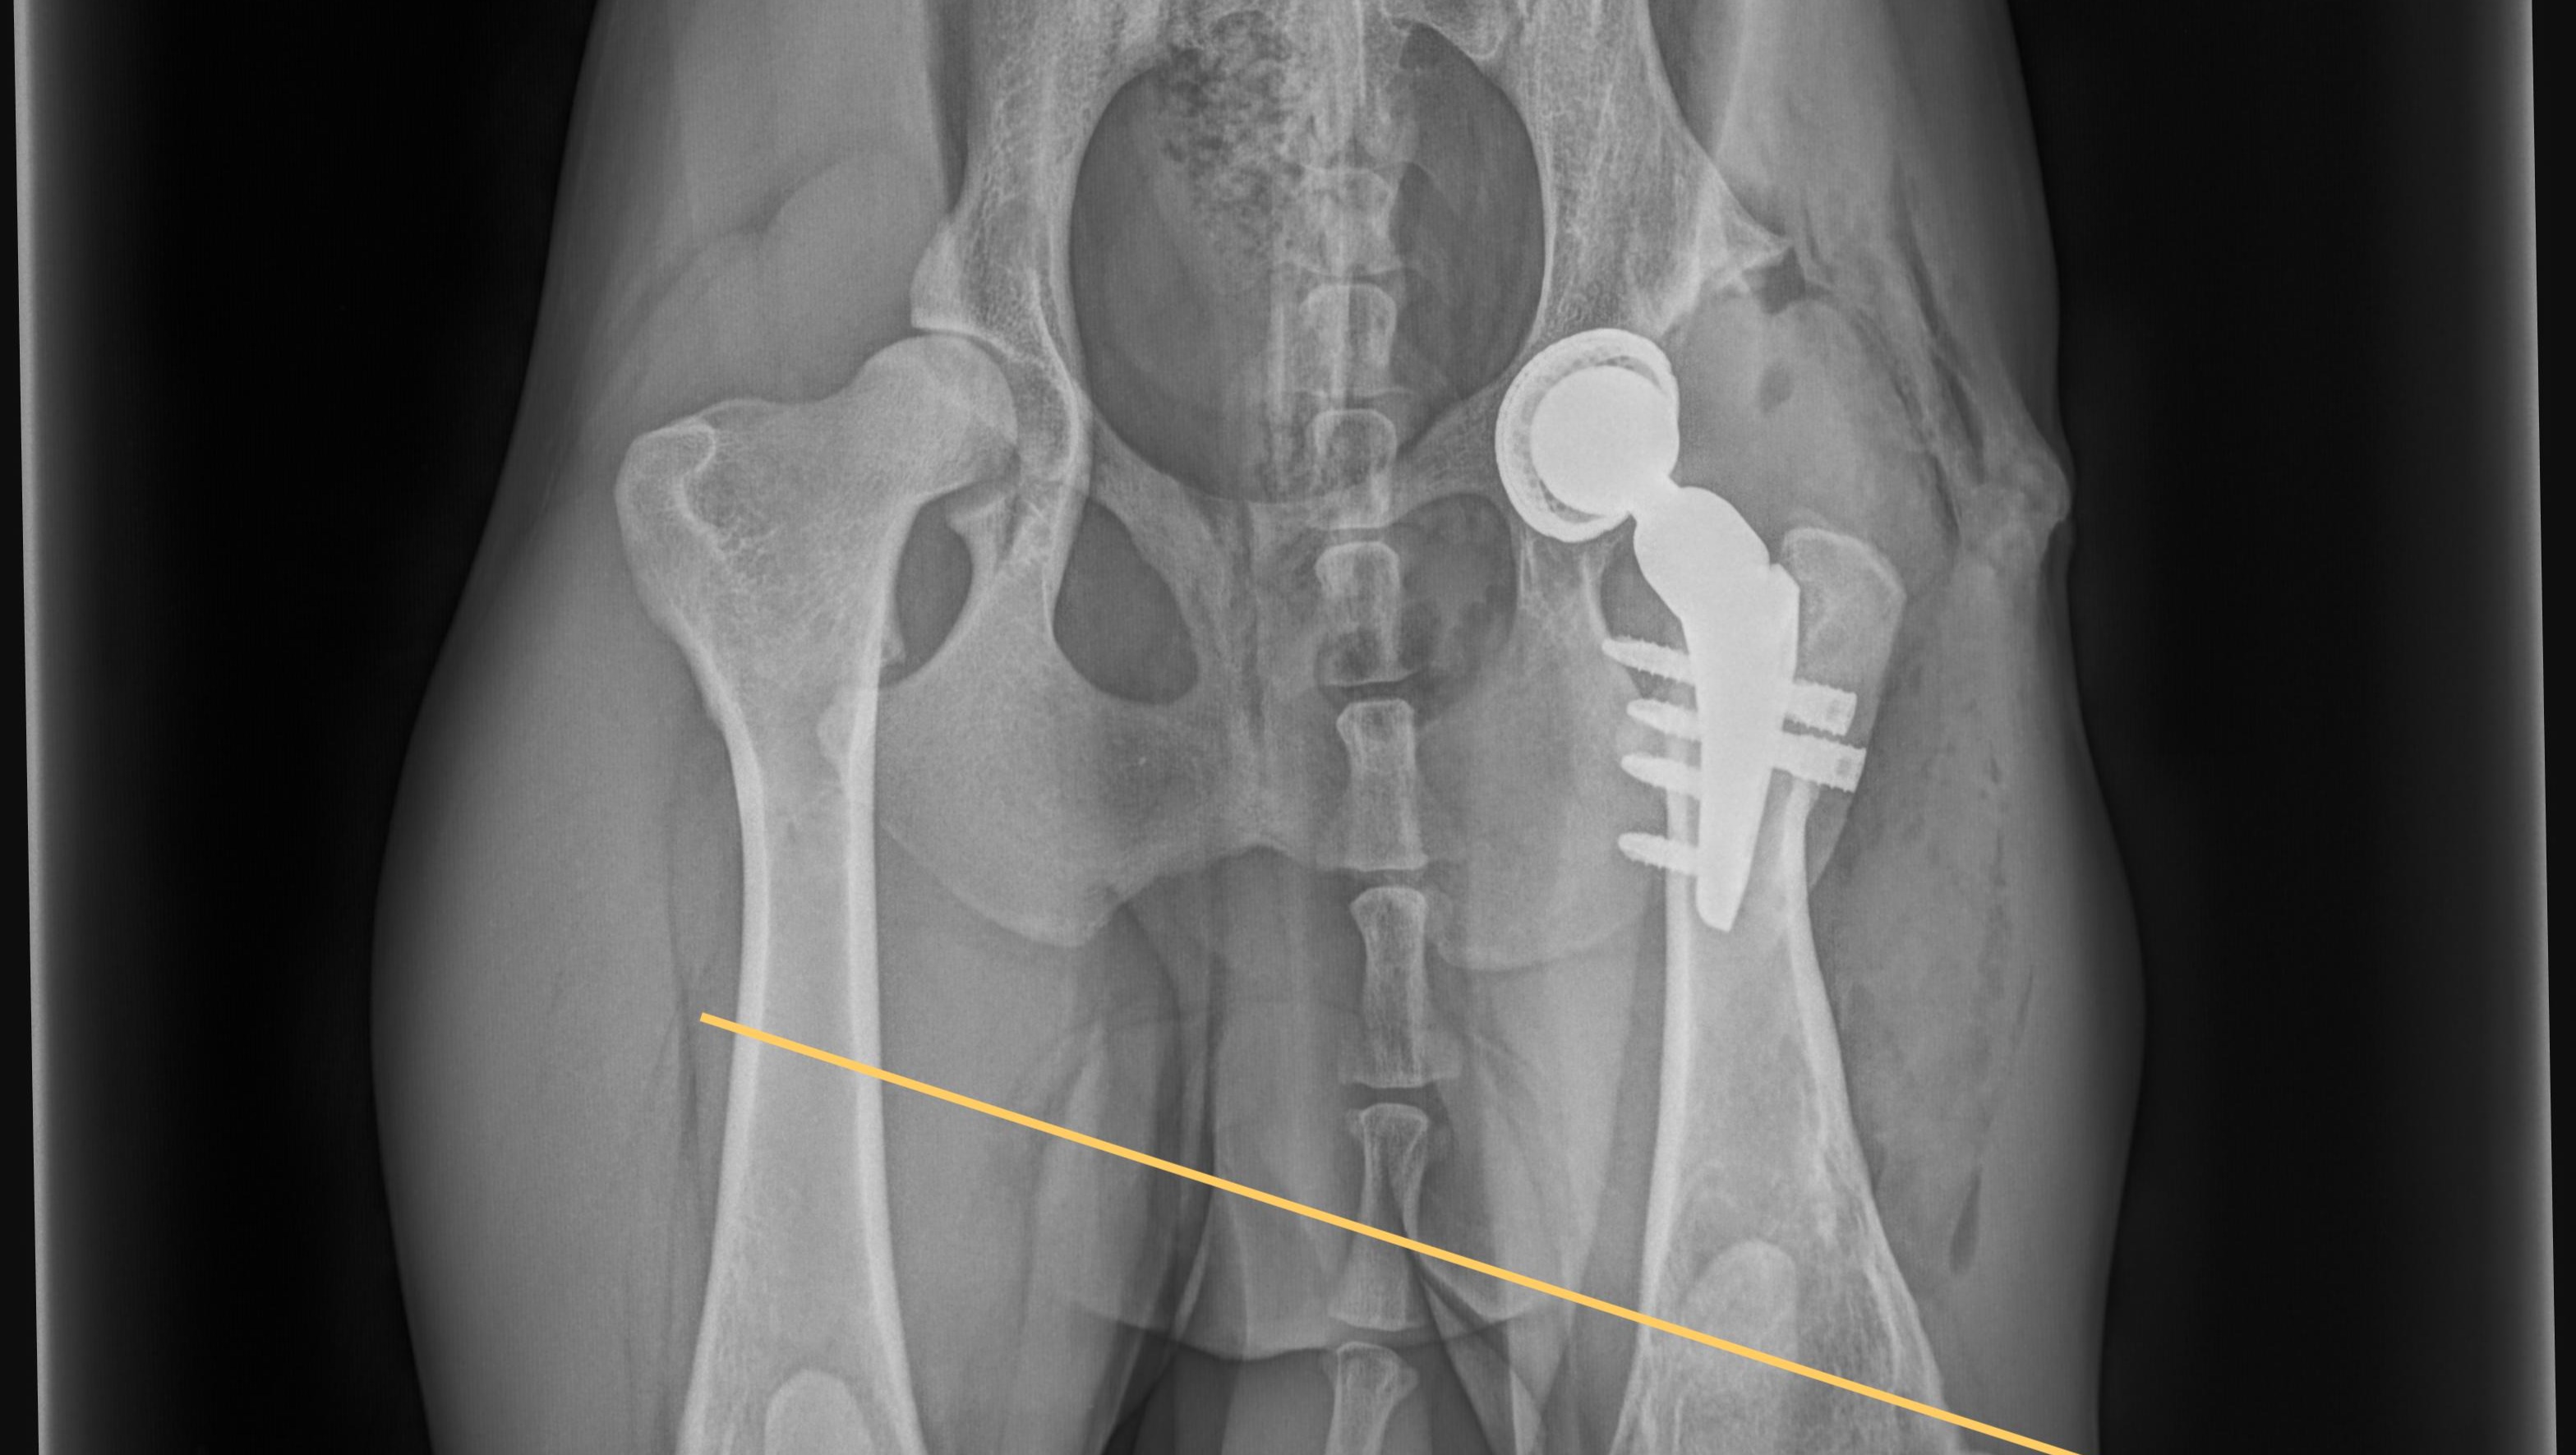

Röntgenaufnahmen und CT-Scans haben zig alte Frakturen und beginnende Arthrosen in seinem jungen Körper aufgedeckt. Ein gerade einmal einjähriger Hund, der bereits mit so vielen physischen Belastungen zu kämpfen hat. Doch die Medizin hat uns nicht im Stich gelassen: Aus seinem Ellbogen wurden Knochenfragmente entfernt, und er bekam ein künstliches Hüftgelenk – ein kleines Wunder der modernen Tiermedizin! Diese Eingriffe bieten ihm die Chance auf ein halbwegs normales Leben.

X-rays and CT scans have revealed countless old fractures and incipient arthrosis in his young body. A dog who is only one year old and already has to deal with so many physical stresses. But medicine has not let us down: bone fragments were removed from his elbow and he received an artificial hip joint - a small miracle of modern veterinary medicine! These operations offer him the chance of a somewhat normal life.